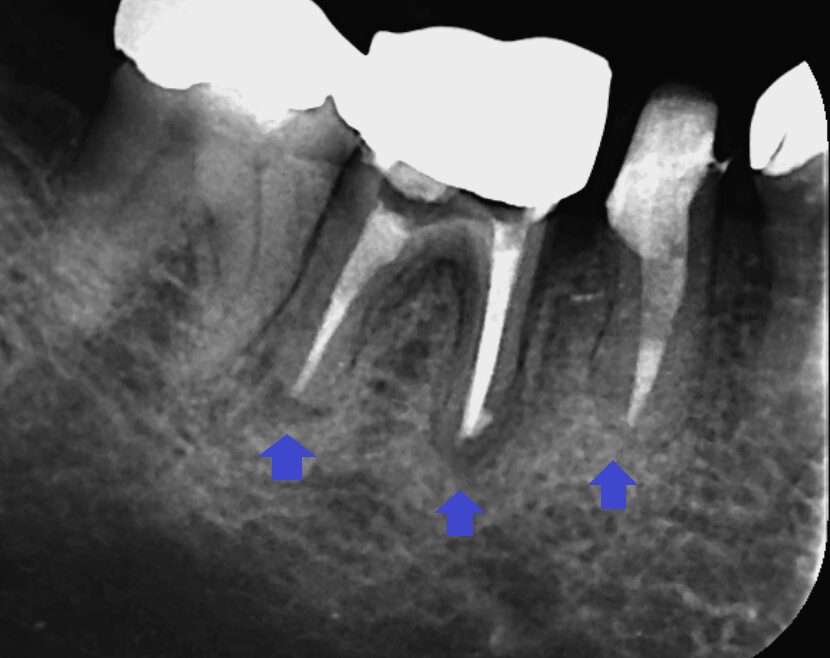

下顎第二小臼歯と第一大臼歯の初診時のCT画像です。

下顎第二小臼歯と第一大臼歯の根の先に膿の影がみられました。第一大臼歯は、2本ある根の両方に膿がみられます。